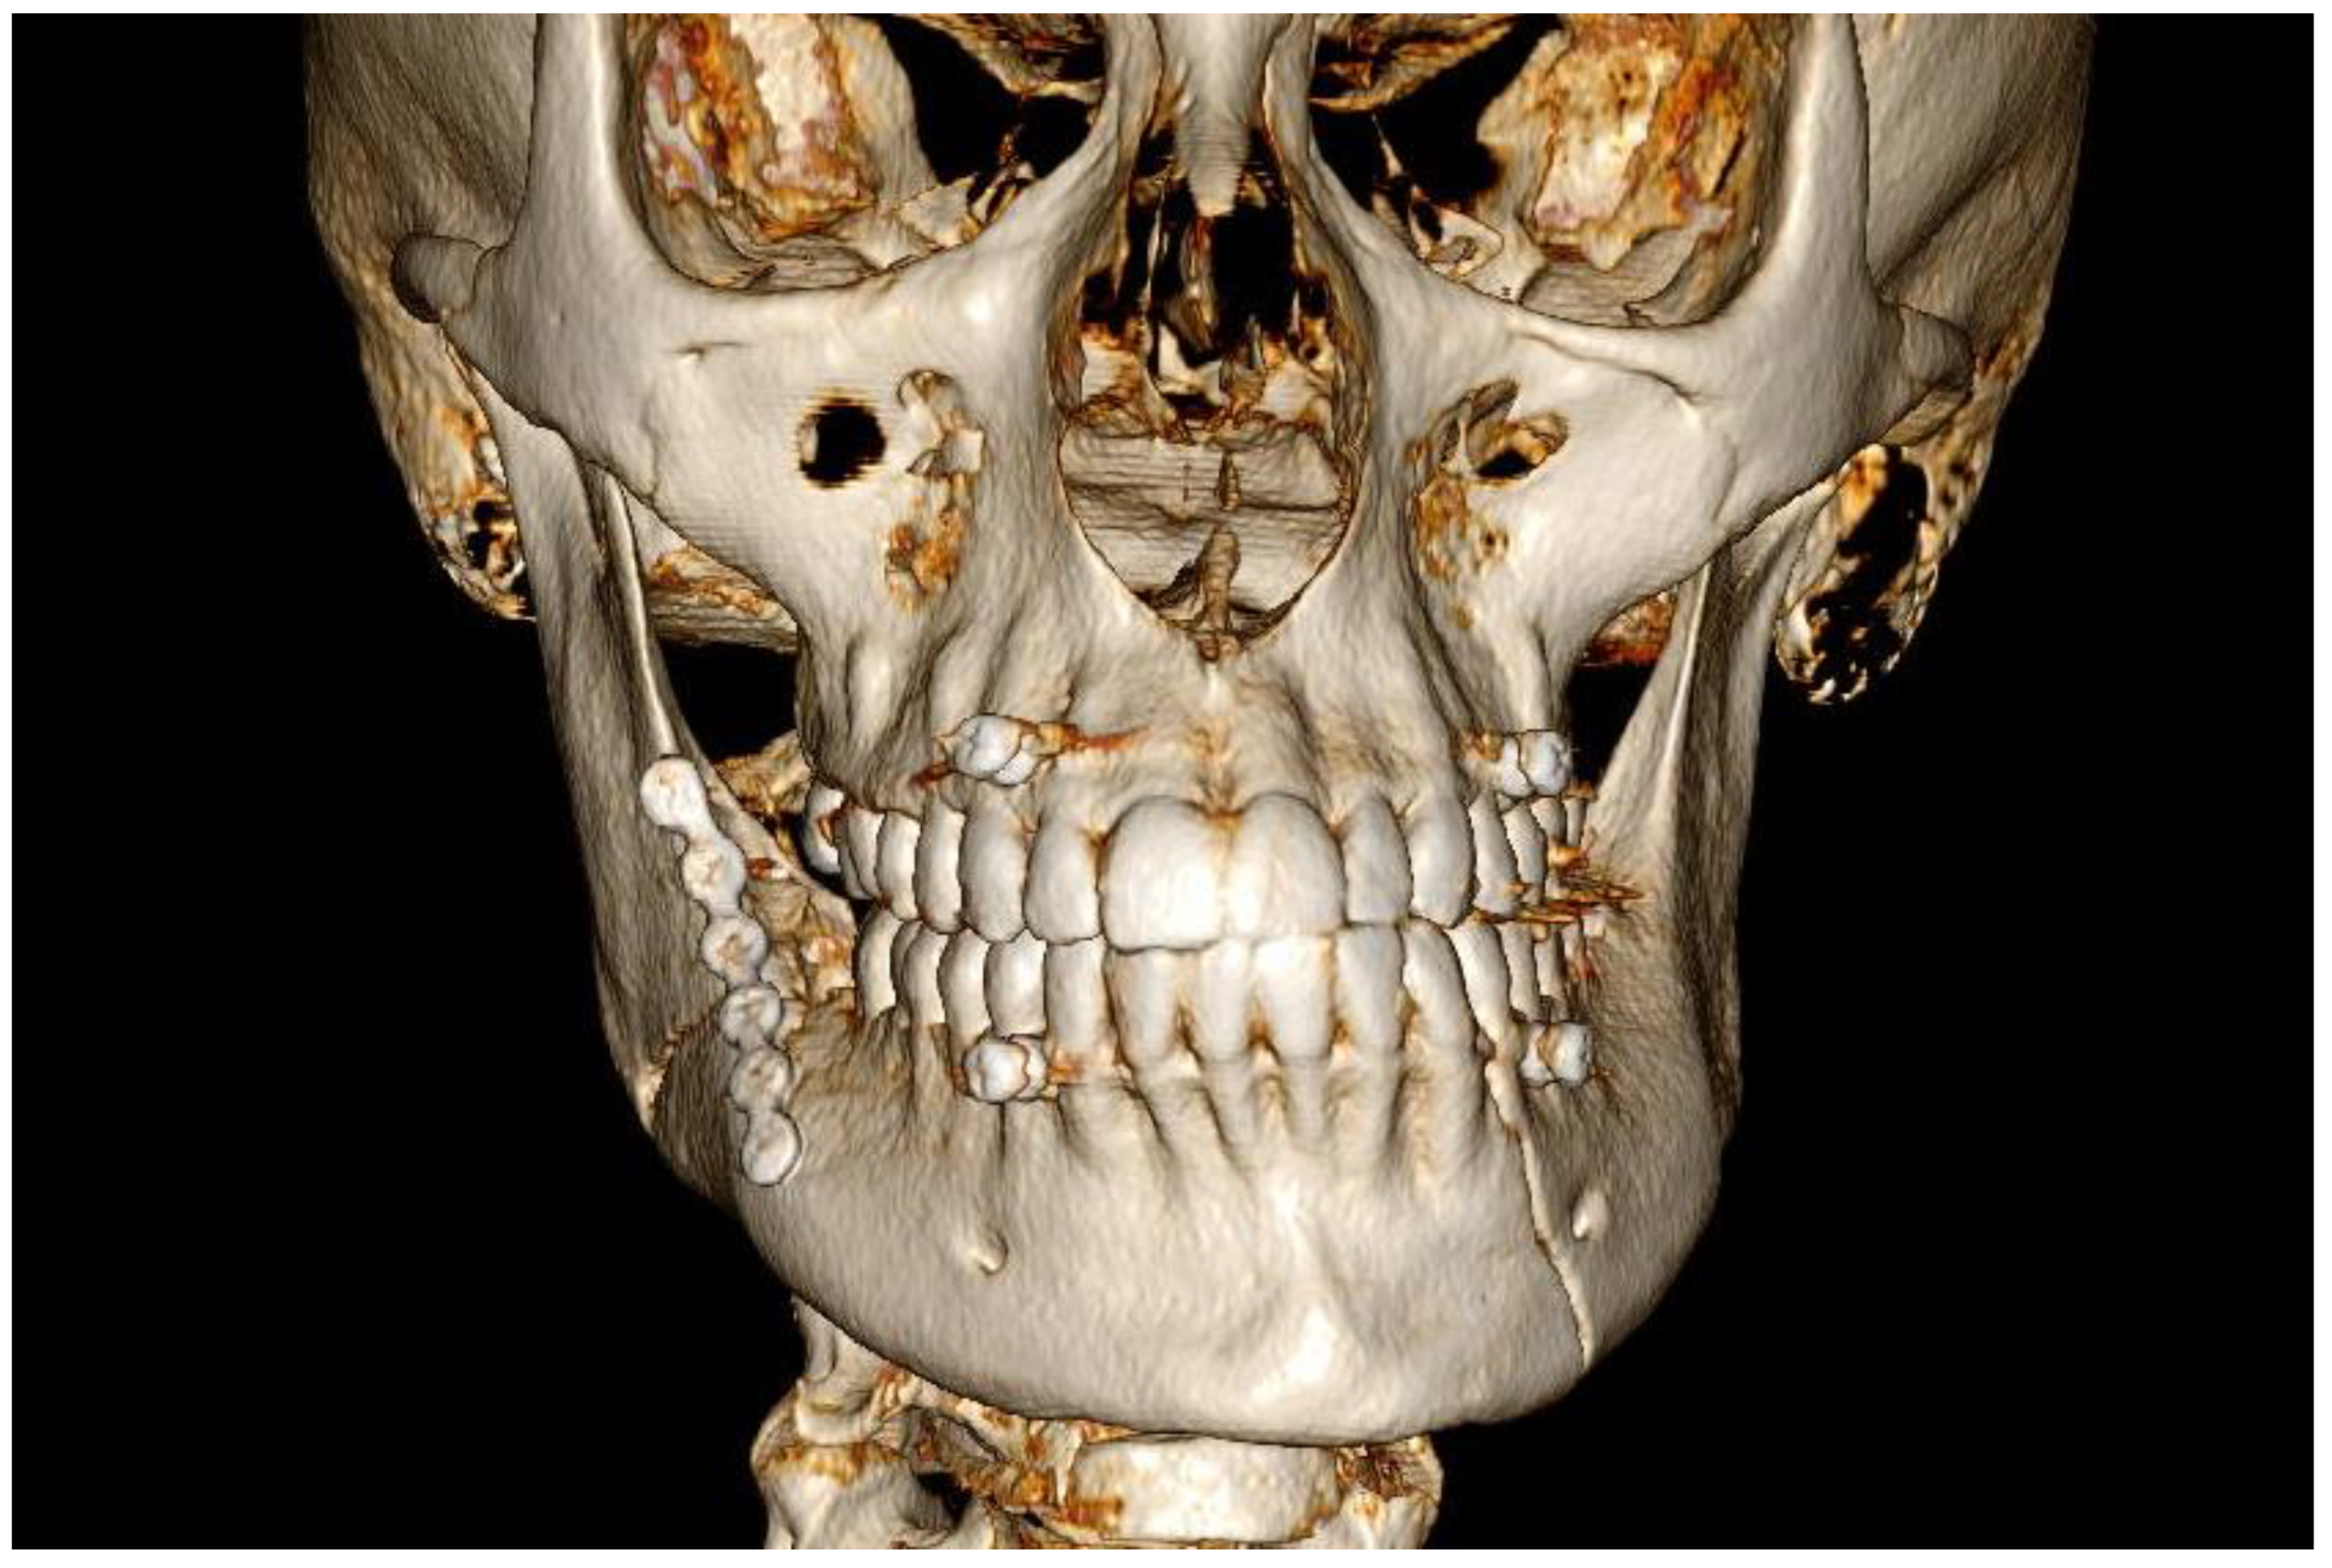

3.2. Case 2

3.3. Case 3

4. Discussion